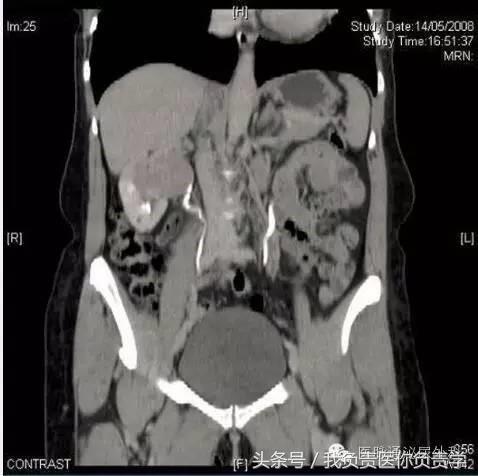

实验室分析(完整血细胞计数、凝血研究和基本代谢检查)显示血红蛋白水平和血小板计数正常,无凝血病。未发现电解质异常。尿液试纸测试未观察到血尿,尿培养阴性。尿细胞学检查对恶性细胞呈阳性。进行膀胱镜检查,显示尿道正常,膀胱由正常粘膜覆盖,未见外生性病变和活动性出血。腹部和盆骨静脉造影CT如图1。

图1

CT尿路造影的轴向图像以及相关的矢状重建,显示右肾盂中存在大面积充盈缺损。充盈缺损延伸并占据右肾盂中多数空间,造成肾造影显影期质量效应和肾脏增强的相对延迟(图2,3)。放射学表现和无痛性血尿及尿液细胞学阳性共同指示上尿路上皮癌。

在该病例中,经患者同意进行了膀胱镜检查,结果显示膀胱正常,未见任何外生肿瘤。CT尿路造影时发现右肾盂中的大面积充盈缺损结合尿细胞学检查阳性,将该患者确诊为上尿路上皮癌。